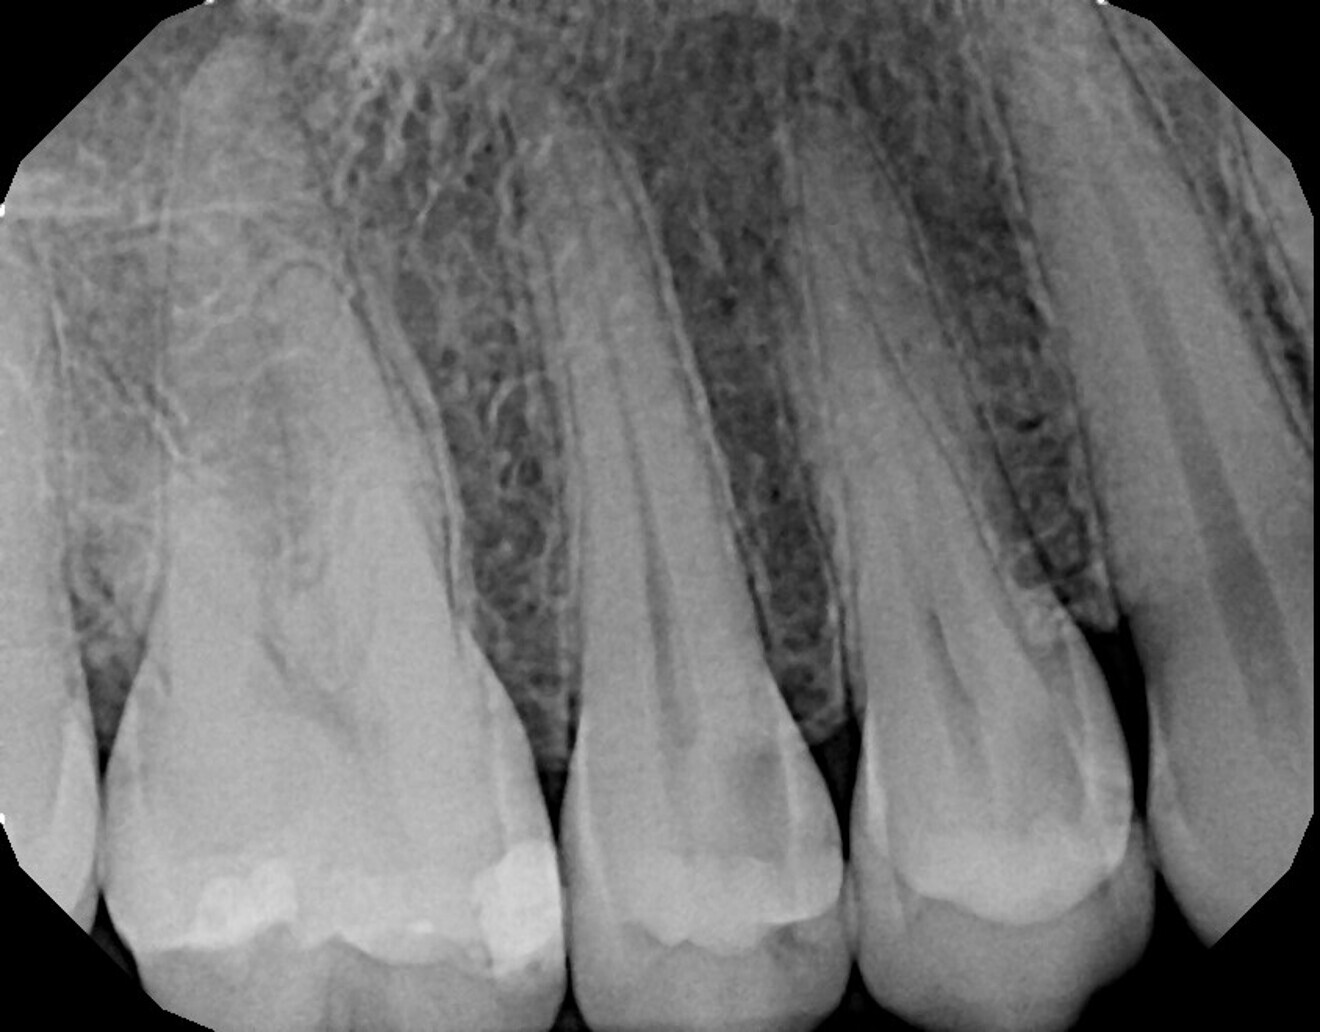

A 53-year-old female patient presented with the complaint of pain in the maxillary left quadrant. Clinical examination noted a missing lingual cusp on the second premolar as well as caries, and a periapical radiograph was taken (Fig. 13). Deep caries was confirmed radiographically, and most of the crown was radiolucent, indicating extensive caries. The outline of the coronal pulp could be observed radiographically, and a lack of periapical pathology was noted. The tooth was tested with cold to verify that the pulp was vital. A mild reaction was noted when cold was applied that immediately resolved when cold was removed from the tooth, indicating that the tooth was vital. The patient was informed that pulpal exposure was expected from caries removal and endodontic treatment would be necessary. After the anticipated endodontic treatment, the tooth would be treated with a post and core and restored with a complete crown. The patient agreed to the recommended treatment.

The patient was seen on recall at four weeks after laser treatment and continued to report a lack of sensitivity to temperature or occlusion. A periapical radiograph was taken, and no periapical radiolucency was noted, indicating that laser treatment of the pulpal exposure had successfully aided in avoiding endodontic treatment (Fig. 17).